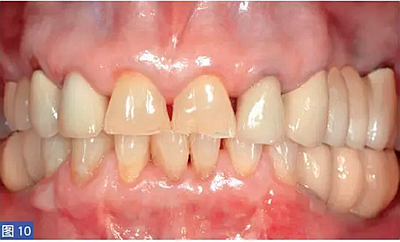

圖10:病例1. 術(shù)后12個月,臨時修復(fù)體。

術(shù)后12個月,調(diào)查患者對治療的滿意程度。VAS 評分如表1 所示。除病例6外,所有患者評最高分。